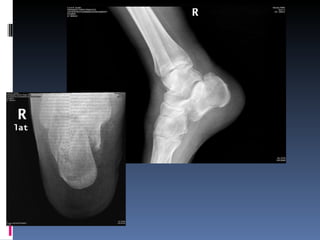

Fractura del calcaneo por insuficiencia

Fractura del calcaneopor insuficiencia